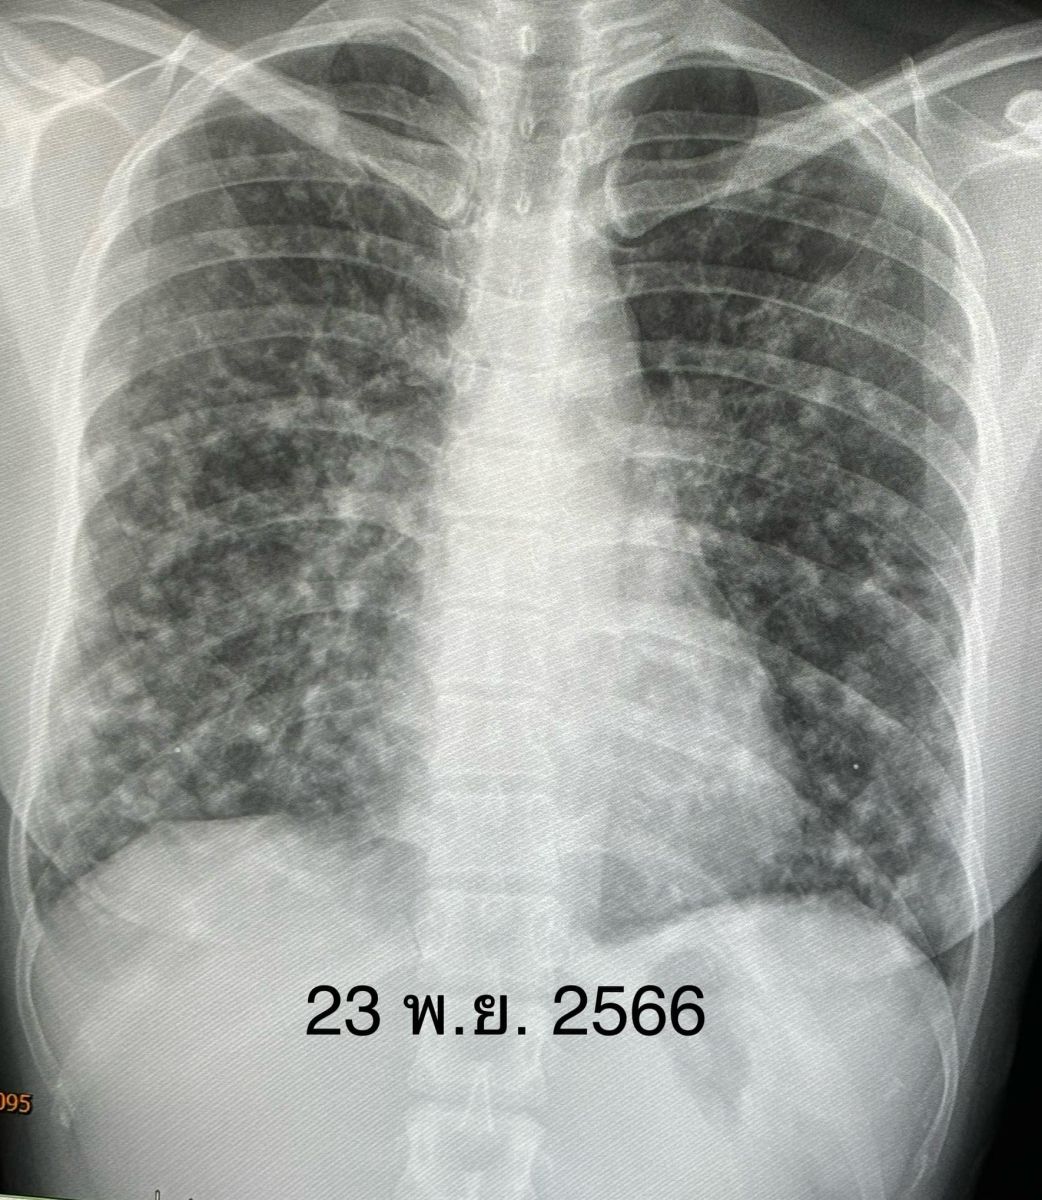

15 กุมภาพันธ์ 2567 นพ.มนูญ ลีเชวงวงศ์ แพทย์เฉพาะทางด้านโรคระบบการหายใจ โรงพยาบาลวิชัยยุทธ โพสต์เฟซบุ๊กรูปภาพฟิล์มเอกซเรย์ พร้อมระบุข้อความว่า ผู้ป่วยหญิงอายุ 38 ปี เป็นโรคเลือดจางและเกล็ดเลือดต่ำ 6 ปี ไม่มียาประจำ ไม่กินเหล้าไม่สูบบุหรี่ ไม่มีอาการ ไม่มีไข้ ไม่ไอ ไม่เหนื่อย น้ำหนักไม่ลด ไปตรวจร่างกายประจำปี เอกซเรย์ปอดพบมีจุดเล็กๆ จำนวนมากกระจายในปอดทั้ง 2 ข้าง

ตรวจร่างกายปกติ ฟังปอดปกติ ระดับออกซิเจนในเลือดปกติ เจาะเลือดเม็ดเลือดแดงและเกล็ดเลือดต่ำเล็กน้อย ค่าตับไต ปกติ ค่ามะเร็งทุกตัวปกติ ทำคอมพิวเตอร์ปอดและช่องท้อง พบจุดเล็กๆ ในปอดขนาด 0.8 เซนติเมตรกระจายทั่วปอด และมีก้อนในตับขนาด 3.4 เซนติเมตร ได้ทำการเจาะเนื้อในตับ ย้อมและเพาะเชื้อ ไม่พบเชื้อราและเชื้อวัณโรค ส่งชิ้นเนื้อตรวจพยาธิวิทยา พบ Epithelioid hemangioendothelioma ติดตามผู้ป่วยนับจากวันที่มีเอกซเรย์ปอดผิดปกติ ถึงปัจจุบัน 6 เดือนแล้ว ผู้ป่วยยังไม่มีอาการ